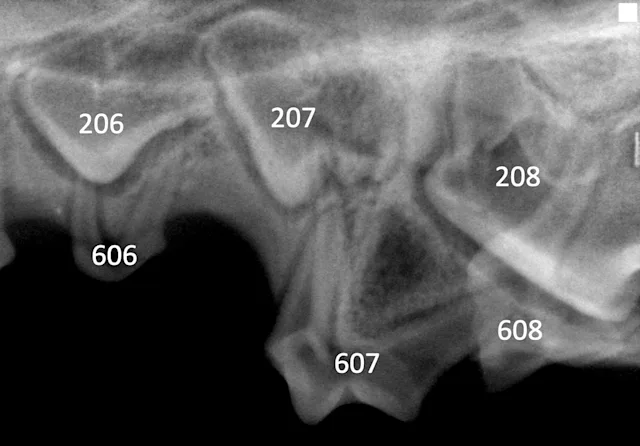

Dental radiography via a veterinary digital intraoral sensor and oral examination were performed with Uma under anesthesia. A slab fracture was seen on the palatal surface of 507 with pulpal exposure (Figure 2); a probe was easily inserted into the pulp cavity. No abnormalities were noted on the left side (Figure 3). Radiographs of the fractured tooth and its contralateral counterpart revealed a radiolucent area at the apexes of the mesial (ie, rostral, side of the tooth directed toward the first incisor) roots of 507.